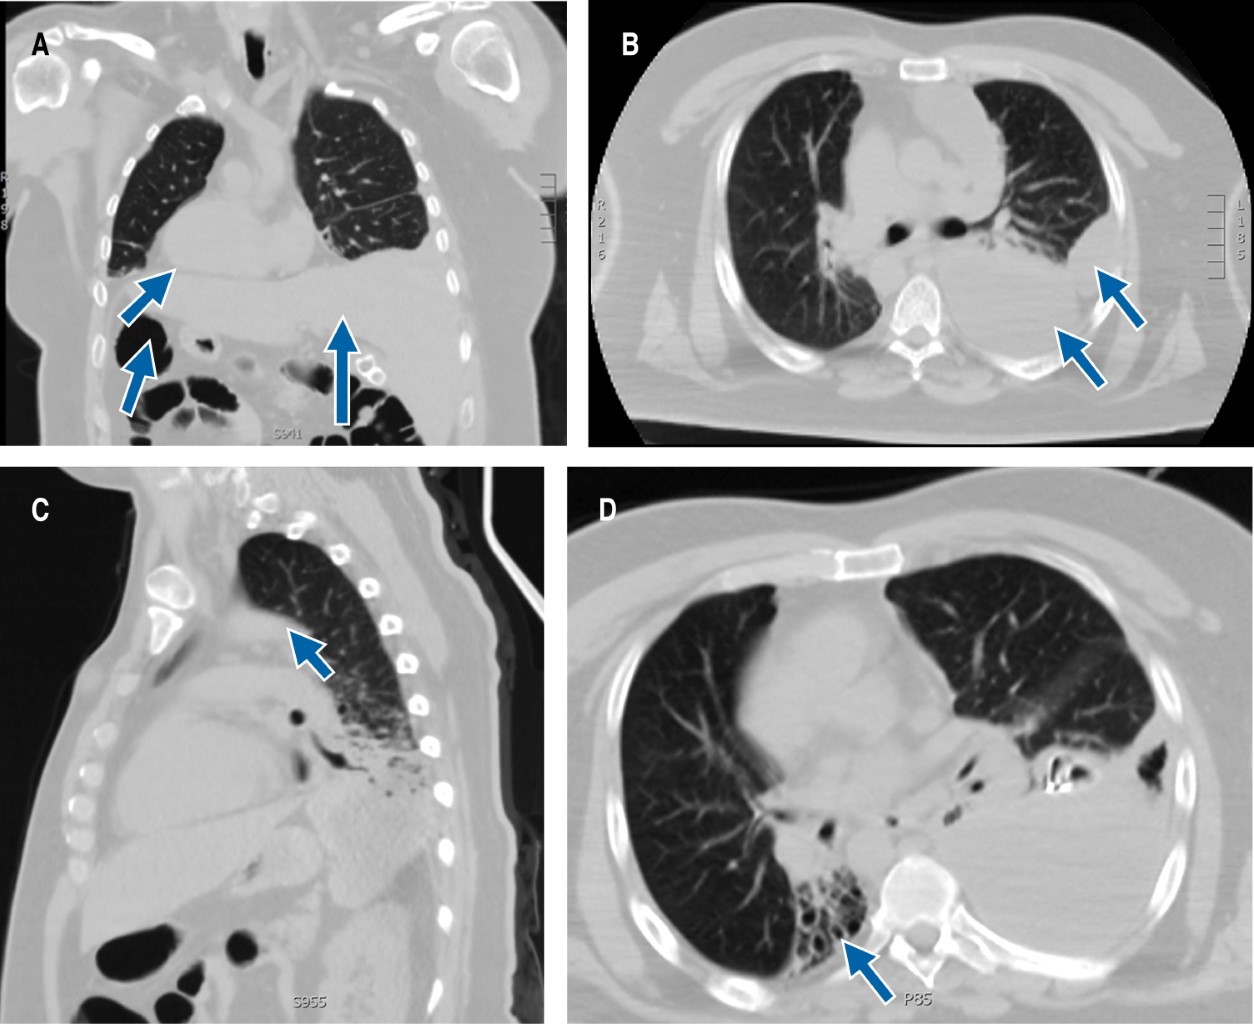

Male patient of 40 years of age, married, without children, with a history of essential arterial hypertension of six-month diagnose in treatment with ARA-II (angiotensin II receptor antagonists), adequate control. History of chronic sinusitis of 31 years of diagnosis without treatment; carrier of situs inversus totalis is reported at nine years of age. Recurrent hospitalization secondary to community-acquired pneumonia, that until now had not conditioned any complication. He began suffering from unquantified fever, shortness of breath and cough, therefore, he is admitted to the emergency area. Laboratory studies were carried out that reported slight leukocytosis at the expense of neutrophilia, increase in acute phase reactant (PCR 50.04), the rest of the paraclinical studies in reference values according to the laboratory. The chest X-ray (not available) showed desxtrocardia, atelectasis, and area of condensation at the base of the right hemithorax; it does not respect the anatomical plane, so it is considered an atypical image. Rapid test is performed for SARS-CoV-2 that is negative. A contrasted computerized axial tomography (CAT) of the chest and abdomen is requested with a report of situs inversus totalis (Figure 1A), mass in the left based and in the anterior mediastinum (Figure 1B and 1C), with slight contrast enhancement, in addition to bibasal bronchiectasis (Figure 1D). Based on laboratory and imaging results, treatment is provided for community-acquired pneumonia (CAP), pneumonia severity index (PSI) of 70 points risk class III, with dual antibiotic treatment. Because the clinic, mainly the cough, did not yield a sputum culture was carried out, with a seven-day growth of Granulicatella elegans; a treatment scheme established by a decrease of 50% the initial PCR value is maintained. Complete course of complicated pleural effusion at the expense of loculations; endopleural probe was placed to try to drain effusion without any success, without obtaining a sample for cytological and cytochemical shipments of pleural fluid. He was moved to the chest surgery area for decortication due to complicated pleural effusion, of probable parapneumonic origin due to repeated infections, secondary to pulmonary dyskinesia with inadequate removal of the ciliary mucus that conditions encapsulation.